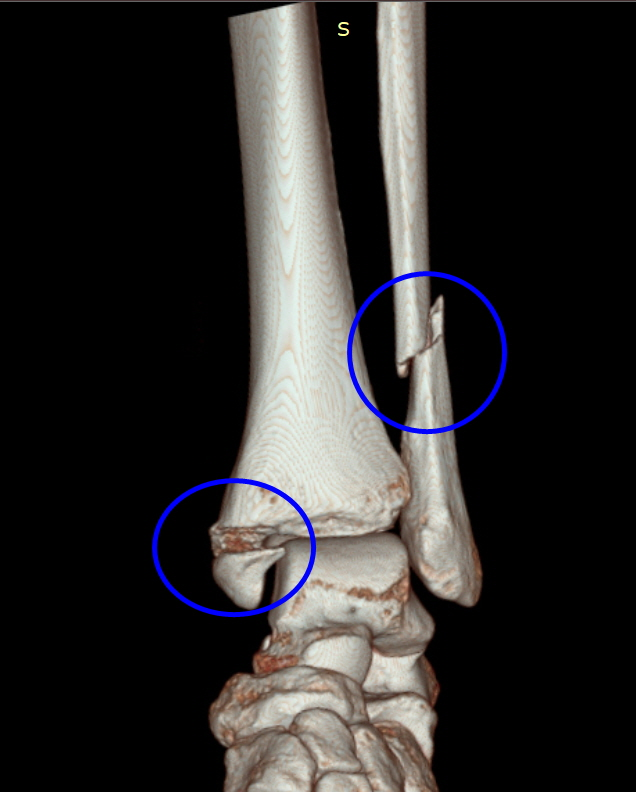

안녕하세요. 오늘 행사는 삼복골절 교통사고 합의 사례입니다.삼복사는 복숭아뼈와 정강이뼈 발목 뒤쪽의 후과를 일컫는 말입니다. 3개의 과(뼈에서 돌출된 부분)를 의미하기 때문에 ‘삼과골절’이라고도 합니다. 덧붙여서 바깥쪽 도골은 경골외과, 안쪽 도골은 비골로 구성됩니다. 위 영상은 전면부이므로 후과골절은 확인이 되지 않습니다. 아래의 X-RAY 영상을 보실 수 있습니다.

피해자는 사고 후 타 병원의 검사 결과 trimal leolar fracture (삼과골절)로 확인되었으며, 수술문제로 상급병원으로 전원 후 관혈적 정복 및 내고정술을 실시하였습니다. 사고로 인한 치료비는 보험사가 지급 보증하므로 걱정하지 마시고, 만약 비급여 치료비를 부담하셨더라도 나중에 영수증 처리가 가능하므로 걱정하지 마시고 치료에만 전념하십시오. 다만 보험사에서 피해자에게 진단서, 수술기록지, 영상판독지, 영상CD 등 다양한 서류를 요구하는 경우가 있는데, 정상적인 지급보증 절차에 필요한 서류는 진단서, 수술기록지 정도이고 영상CD는 추후 후유증 관련 분쟁시 불리할 수 있으므로 추후 제출하는 것이 좋습니다.

왼발관절 삼복사골절 왼발관절부 피부괴사 왼발관절경비인대결합파열 시점은 언제가 좋을까요